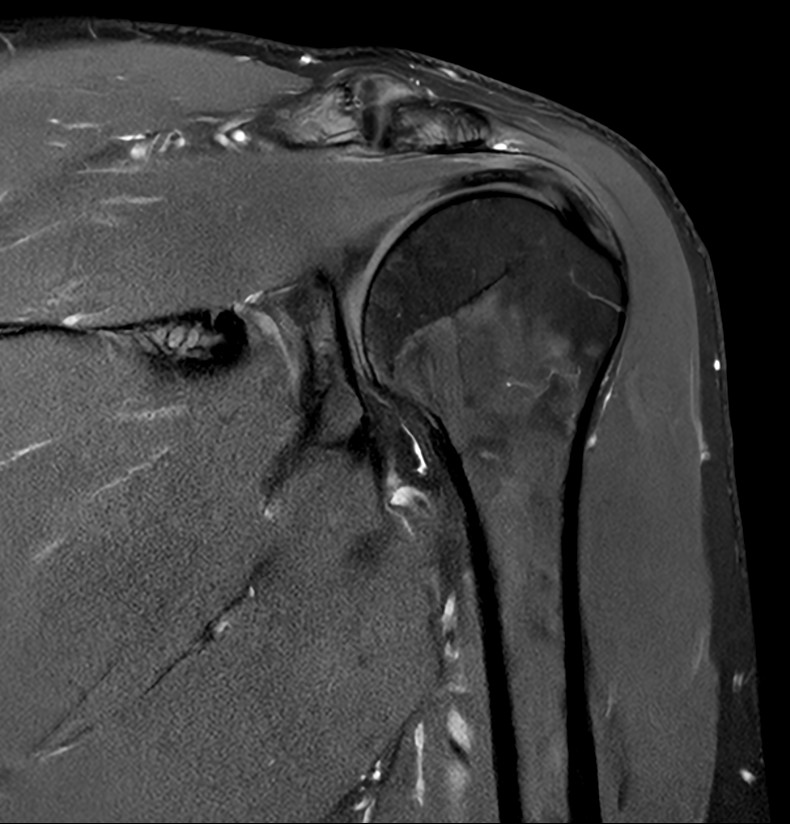

High quality Shoulder imaging with SmartSpeed Precise